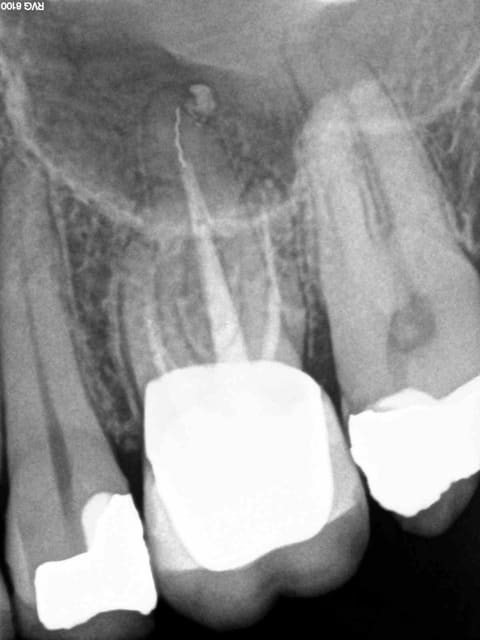

Ceram à refaire sur cette 26 facile : dépose , rectification de préparation empreinte, provisoire ( 20 mn) et pose. Sauf que le sc 33 initial est resté dans la provisoire à la dépose de celle ci.-))

Pas grave j' y ai recollé un screw post titane (screw pol de chez apol) avec du mimesis DC ( composite dual multi usage) après avoir apprêté l'intrados de la couronne et le reste de la dent au peak universal bond.

C'est quoi qui te gène ? Le fait de ne pas se faire chier à faire une RTE ( a vrai dire pas de signe radio de pèche) ? ou de faire un sc33 après la couronne ? -))))

Tu es sur que l'apex de la palatine va bien? Simple question

Elle a l'air très bien cette 26. Je suis sûr qu'elle est comme ça depuis 10 ans. Pas de symptôme, image radio n'est pas préoccupante: j'aurais fait comme l'ingénieux Chicot. En ces temps difficiles, épargner les maigres ressources de l'assurance maladie est un devoir national. Un SC33 au lieu de endo, radios, SPR57, me parait être une conduite de la plus stricte économie. Ceux qui veulent retraiter cette 26 sont de mauvais Français.

Voilà, pas de signe d'appels, la plus stricte économie, pas de signes radios 2D (lol!) et cerise sur le gateau une seule radio post op, gestion en bon père de famille comme ca pas besoin de se rattraper sur la prothèse -))))

Je ne voudrais pas jeter de l'huile sur le feu mais ce qui me gène le plus n'est pas l'éventuelle pêche sur la racine palatine mais plutôt que sur la radio de contrôle la couronne n'est même pas en place avec un hiatus en mésial et une marche en distal.

ça veut dire que le pauvre patient va inéluctablement perdre sa dent dans un délai relativement court soit par carie sous gingivale, soit par problème paro sans parler du manque d'étanchéité du composite et de la perte du point de contact distal.

Edit: et j'avais même pas vu la photo avec la pointe du tenon noircie par la percolation bactérienne dans le canal palatin ... effectivement pas besoin de RTE.

1. Ne pas se fier aux radios dont les images dépendent de l'incidence.

Le soucis, dans le cas présent, est qu'il y aura surement un abcès dentaire dans moins de 2 ans sur cette dent... Du moins c'est fort probable.

Ce gros screw post en se descellant a surement rompu un équilibre précaire qui faisait que cette obturation canalaire médiocre au demeurant n'avait pas déjà eu pour conséquence un joli granulome.

En l'occurence, le reste de gutta du canal a surement été descellé aussi au cours de la manœuvre.

Et cela aboutira dans quelques mois à ce qui est communément appelé une pêche...

Je trouve juste que tu as pris un risque sur ce coup là. Autant, je suis contre le retraitement systématique (quand il n'y a pas de symptôme), autant lorsque je me retrouve dans le canal et qu'il est mal obturé radiologiquement parlant, je pense que pour être plus serein, il vaut mieux retraiter...